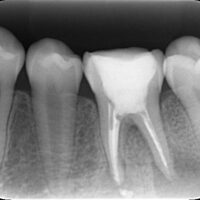

特に注目すべきは、「初回治療が根管の形態にどのような影響を与えたか」が、再治療の成功率に大きく関係するという点です。この論文では、初回治療で根管の自然な形態を保持できた場合と、形態が変更された場合を比較し、それぞれの成功率を具体的な数値で示しています。

全ての対象歯を2つの主要なグループに分類しました。

1. Root-canal morphology respected group

初回治療で根管形態が保持された歯

2. Root-canal morphology altered group

初回治療で根管形態が変更された歯

• Root-canal morphology respected group(根管形態が保持された歯):

成功率は86.8%

• Root-canal morphology altered group(根管形態が変更された歯):

成功率は47%

この研究の結果は、再治療の成功率は初回治療での根管形態の扱いに大きく依存することを示しています。具体的には、初回治療で根管の自然な形態が保持されていた場合、再治療の成功率が非常に高い(86.8%)ことが分かりました。一方で、初回治療で根管形態が変更されていた場合、成功率は47%に低下しました。

• 根管形態が変更されると、自然な解剖学的構造が失われ、感染のリスクが増加する可能性があります。

• また、変更された形態では、再治療時に感染源を完全に除去することが難しくなるため、成功率が低下する可能性があります。